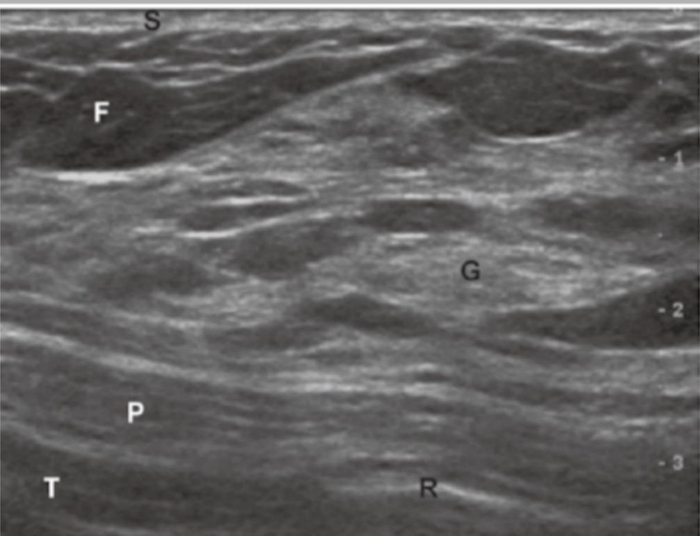

只有在合适的时间进行乳房B超检查,才可以清晰地显示从皮肤表面到胸壁的乳腺解剖结构[4]。

正常乳房的超声影像,显示乳腺解剖结构[4]